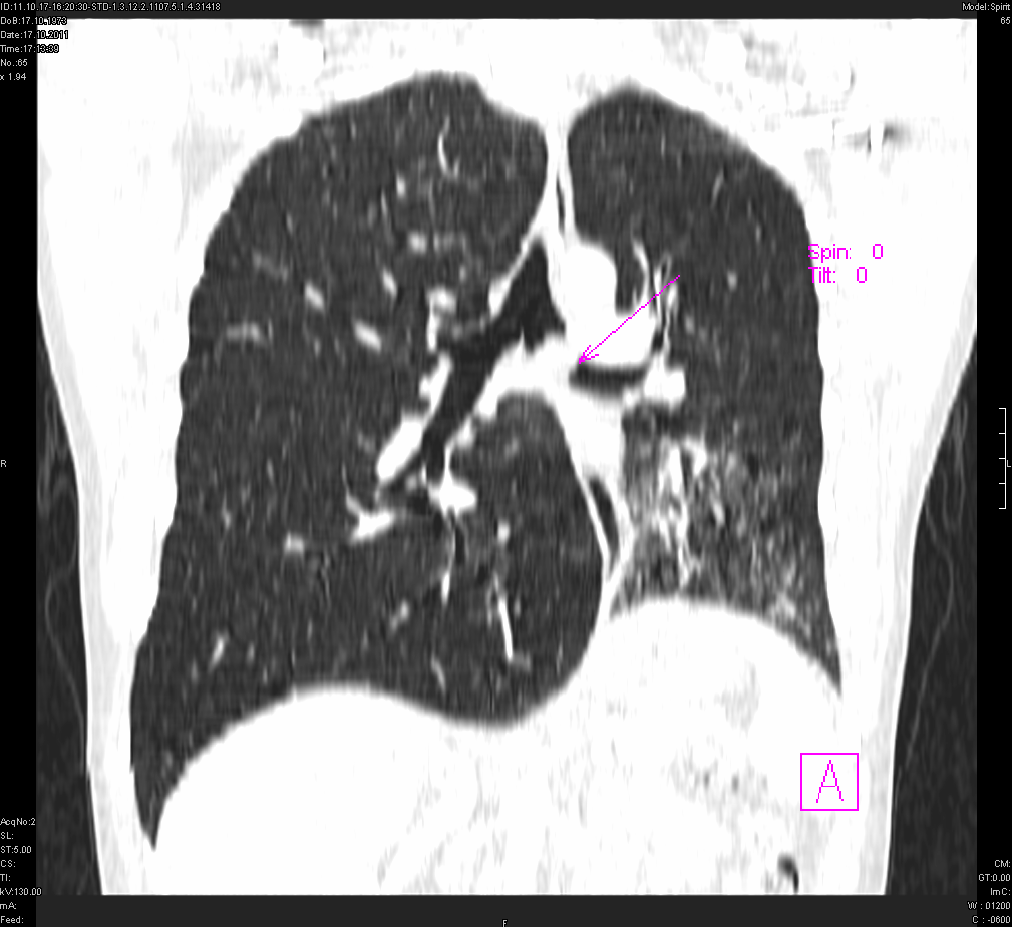

- გულმკერდის კტ (Coronal) რეზექციამდე 5 თვით ადრე

გულმკერდის კტ რეზექციამდე (Coronal).